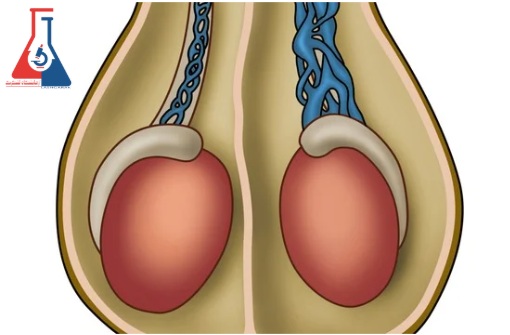

واریکوسل (Varicocele) بزرگ شدن وریدهای داخل کیسه شل پوستی است که بیضه ها (اسکروتوم) را نگه می دارد. این وریدها خون کم اکسیژن را از بیضه ها منتقل می کنند. واریکوسل زمانی اتفاق میافتد که خون در سیاهرگها جمع میشود، نه اینکه به طور موثر از کیسه بیضه گردش کند.

بیضه ها خون غنی از اکسیژن را از دو شریان بیضه دریافت می کنند – یک شریان برای هر طرف کیسه بیضه.

به طور مشابه، دو ورید بیضه نیز وجود دارد که خون تخلیه شده از اکسیژن را به سمت قلب برمی گرداند.

در هر طرف کیسه بیضه، شبکهای از وریدهای کوچک (شبکه پامپینیفرم) خون فاقد اکسیژن را از بیضه به سیاهرگ اصلی بیضه منتقل میکند.

واریکوسل بزرگ شدن شبکه پامپینی فرم است.